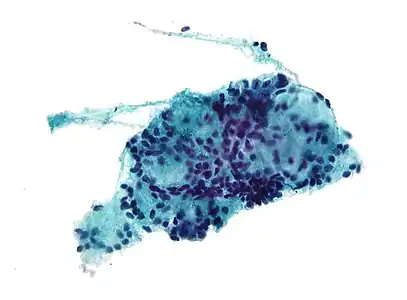

Histopathological image of adenoid cystic carcinoma of the salivary gland, immunostain for S-100 protein Micrograph of adenoid cystic carcinoma, fine needle aspiration specimen, Pap stain

Micrograph of adenoid cystic carcinoma, fine needle aspiration specimen, Pap stain Adenoid cystic carcinoma with comedonecrosis